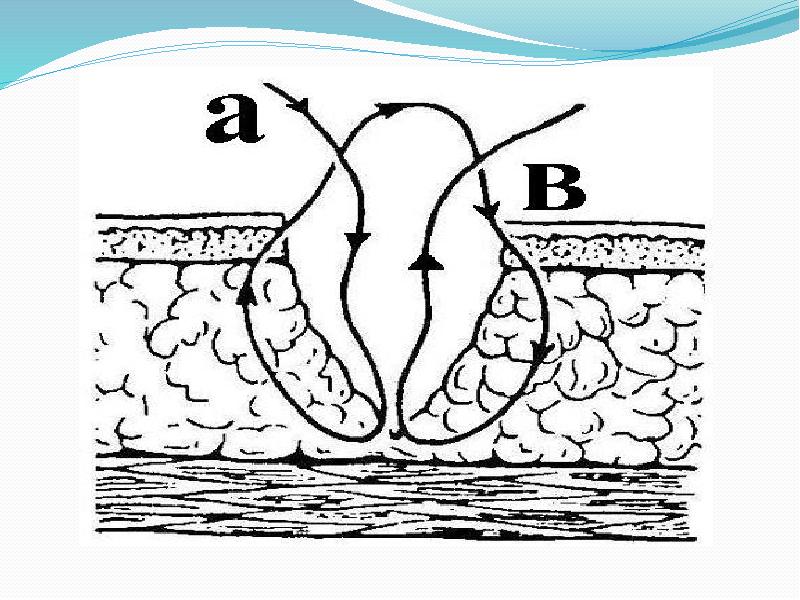

- 55. Внеэпидермальный обратный узловой шов (по Эбади) является основным видом кожного шва в современной

- 57. Схема сопоставления краев раны и расположения узла после наложения внеэпидермального обратного